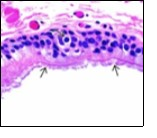

Alternatively, cutaneous ciliated cyst can be lined by non ciliated cuboidal or columnar epithelium with intermingled intercalated, dark or round peg cells. Foci of squamous metaplasia can be occasionally exemplified in the adherent epithelium whereas mucinous cells or apocrine-like features are exceptional 6, 8. Figure 1, Figure 2, Figure 3, Figure 4, Figure 5, Figure 6, Figure 7, Figure 8, Figure 9, Figure 10, Figure 11, Figure 12. 11, 12, 13, 14, 15, 16, 17, 18, 19.

Figure 3.Ciliated cutaneous cyst with a coating of plump, ciliated columnar epithelium and a circumscribing fibro - connective tissue (12).